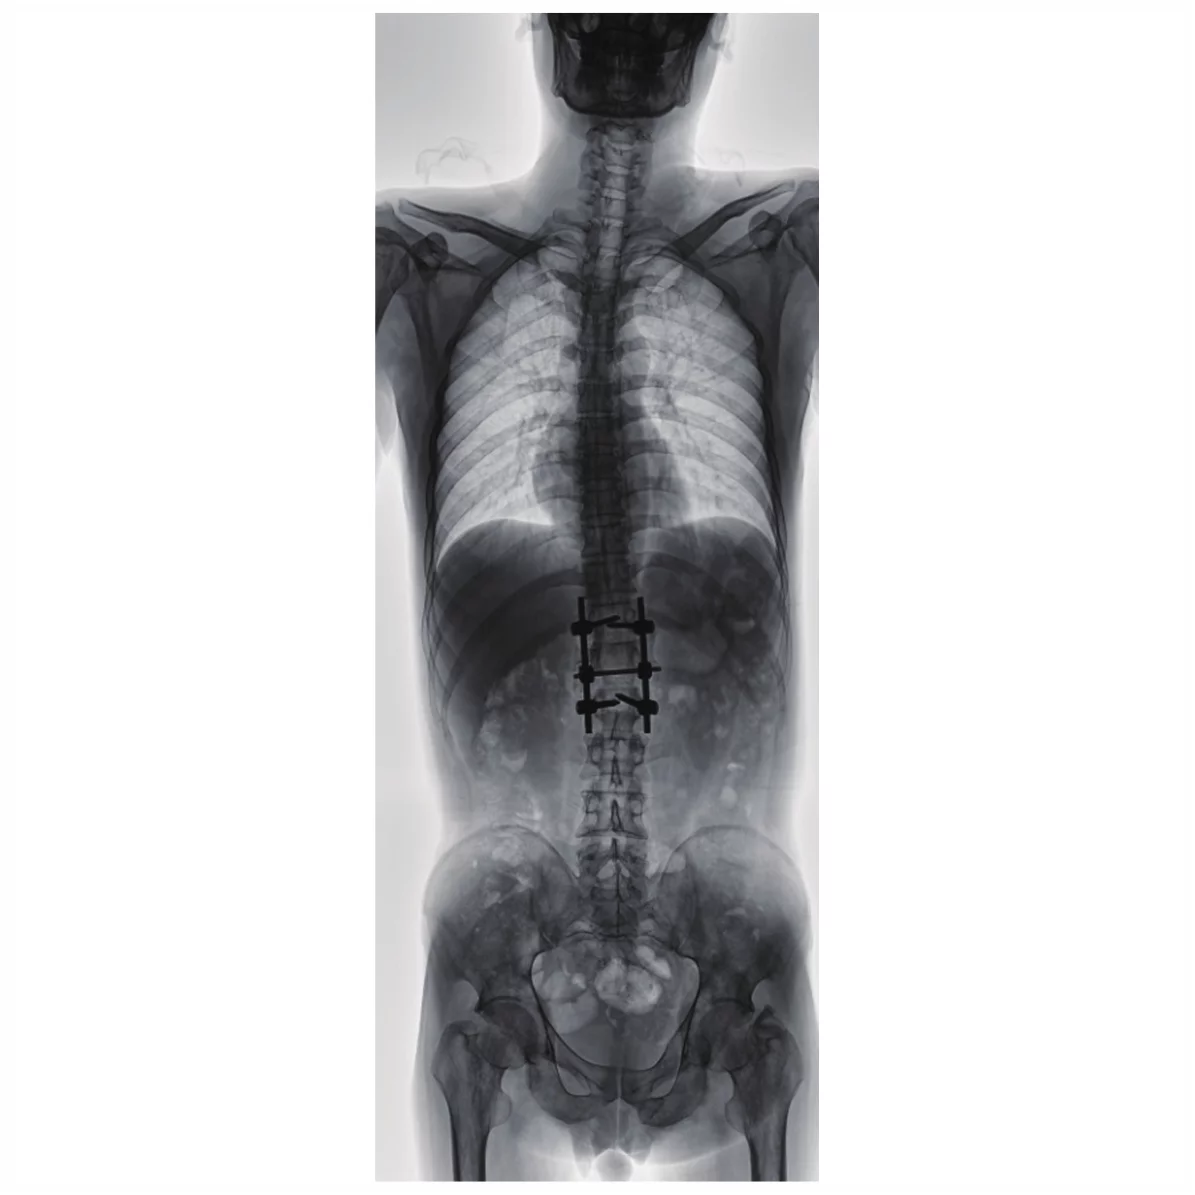

- Новая автоматическая система контроля дозы, получение более четкой информации об изображении при меньшей дозе облучения, снижение радиационного воздействия на врачей и пациентов. Интеллектуальное управление Ориентированность на людей и высокий уровень заботы Гибкое и эффективное многомерное перемещение Полное удовлетворение в различных положениях. Умные инновации Полнофункциональный динамический FPD Отличное изображение с широким охватом 17*17 большой размер динамического FPD, который обеспечивает большую площадь захвата, широкое поле изображения и полный охват изображения. Высокая частота кадров Высокая частота кадров позволяет получать изображения высокой четкости в динамическом режиме так же, как и в статическом. Самая высокая скорость съемки может достигать 30 кадров/секунду, четкие и гладкие динамические изображения. Функция автоматической сшивки Сколиоз и несущая деформация скелета нижних конечностей, предоперационная и послеоперационная панорамная съемка может непосредственно отражать степень и расположение поражения, обеспечивать надежную диагностическую основу для клинической практики. Полный позвоночник, полная панорамная съемка нижних конечностей, достижение одномоментной рентгенографии во время наблюдения сколиоза от шейного позвонка до хвостового позвонка или других повреждений.